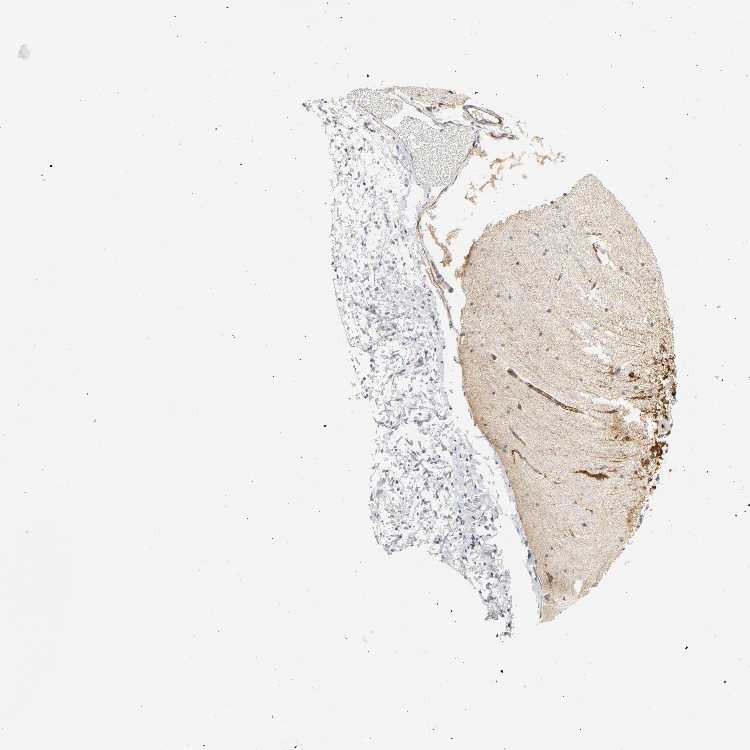

CEREBELLUM - Antibody stainingi

Antibody staining in the annotated cell types in the current human tissue is reported as not detected, low, medium, or high, based on conventional immunohistochemistry profiling in selected tissues. This score is based on the combination of the staining intensity and fraction of stained cells.

Each image is clickable and will lead to virtual microscopy that enables deeper exploration of all samples and also displays staining intensity scores, fraction scores and subcellular localization as well as patient and tissue information for each sample.

Antibody HPA048692Antibody CAB004378

Purkinje cells Not detectedNot detected

Cells in granular layer Not detectedLow

Cells in molecular layer Not detectedLow